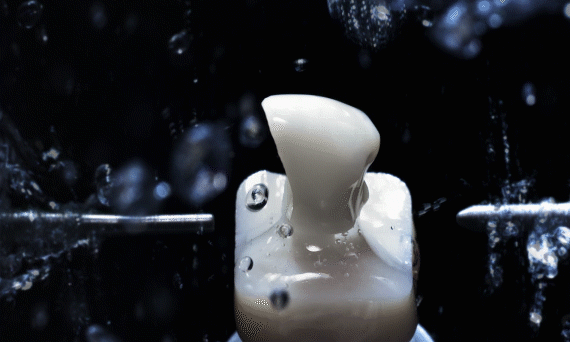

传统制作牙冠需要取模、切削、烧结、上瓷、上釉等8个步骤,一个环节错误就会导致数据失准,出现误差,现在通过数字化CAD/CAM设备,精确到微米,制作假牙的时间可以提速到2小时,就能完成最终戴牙,修复效率大大提高。

一整套的数字化设备可以让患者能够实现当天种植,当天带牙,当天就能吃苹果。

通过德国CAD/CAM中心的数字化设备,为患者完成个性化基台和临时牙冠的制作。经过高科技仪器的精密打磨与切削,与患者缺牙位吻合的牙体即在术前整备完好,等待着填充患者缺牙位置,实现即刻负重。

全套德国数字化极简种植真正做到术前种植方案可预见,种植效果可预知,种植牙体可预成。